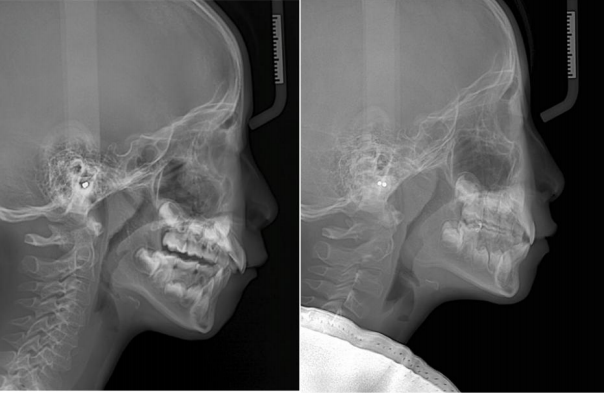

这位6岁的小朋友主诉嘴凸、没下巴、牙齿不齐,家长的早矫意识比较强,决定让小朋友及时进行早期矫正干预。

通过牙片资料检查孩子有骨性II类倾向,重度深覆合深覆盖,牙齿存在散在间隙。第一阶段佩戴隐形牙套,隐形矫正结束后,上颌内收,颏部前伸,侧貌形态改善良好,前牙达到正常覆合覆盖。

这位11岁孩子主诉嘴凸、下巴后缩,家长带孩子来做矫正,也是怕来晚了,孩子嘴凸、下巴后缩会越来越严重。

考虑到孩子还在生长发育阶段,还有一定的生长潜力,综合考虑孩子的牙齿、面型情况之后,制定不拔牙矫正方案,使用隐形牙套。

关键一点是通过推磨牙向远中+扩弓来获得间隙,解决前后牙距离大、内收排齐牙齿、把上下牙角度调直,调整咬合平面角度,创造下巴前伸的条件。